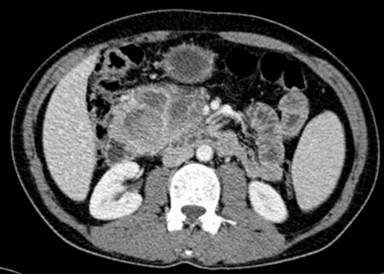

A 58-year-old man not known to have any pre-existing medical conditions was admitted with a one week history of melena requiring frequent blood transfusions. He denied any abdominal pain or vomiting. However, his appetite had decreased and he had significant weight loss. Examination revealed anemia and a non-tender firm mass in the epigastrium measuring about 10x9 cm. An upper gastrointestinal endoscopy showed an ulcerative growth occupying the medial wall of the second part of the duodenum extending into the third part. The morphology and immunohistochemistry of the biopsy from the lesion were highly suggestive of an aggressive gastrointestinal stromal tumor. Contrast-enhanced CT showed a 10x9 cm, heterogeneous, hypervascular mass in the sweep of the duodenum inseparable from the duodenal wall and the pancreatic head (Figure 1). The mass was predominantly solid, admixed with minimal cystic components. The superior mesenteric vessels were intimately related to it. There was no retroperitoneal lymphadenopathy noted. No focal lesions were seen in the liver. Multiplanar, multisequential MRI of the abdomen with contrast confirmed the above findings and the hypervascular necrotic nature of the mass, suggesting a gastrointestinal stromal tumor. Tumor marker studies were negative for CA 19-9, alpha-fetoprotein and CEA. In view of the bleeding nature of the tumor which could not be managed with frequent blood transfusions (he had received daily transfusions for 4 days and his hemoglobin level remained at 7 g/dL (reference range: 12.5-15.5 g/dL)), the patient underwent a pancreaticoduodenectomy. Laparotomy revealed a nodular tumor measuring about 10x9 cm arising from the 2nd and 3rd parts of th duodenum and extending into the infracolic compartment in proximity of the superior mesenteric vessels. No gross metastases in the liver or peritoneum were noted. The patient underwent a pancreaticoduodenectomy (Figures 2 and 3). A right hemicolectomy was also performed as, in the process of excising the tumor, the right hemicolon appeared dusky. The patient made an uneventful recovery except for a superficial surgical site infection. The histopathology report confirmed the gastrointestinal stromal tumor with predominant spindle cells and a mitotic figure of more than 10 per 50 high power field (HPF) (Figures 4 and 5). Wide areas of tumor necrosis and marked nuclear pleomorphism were also noted. The margins were negative for tumor and no metastasis was noted in the 12 regional lymph nodes which were excised. Immunohistochemical stains were strongly positive for CD117, focally positive for CD34 and negative for epithelial and muscle markers (Figure 5). The patient was started on imatinib 400 mg bid at the 2nd postoperative week. His response to imatinib mesylate was very modest, if at all, and he presented with widespread intra-abdominal recurrences 12 weeks after surgery, confirmed by a CT scan-guided Trucut biopsy. The patient eventually succumbed to his disease 6 months after the surgery.

Figure 1. Contrast CT scan revealing a large mixed echogenic mass arising from duodenum and involving the pancreas. |

CT and MRI are the best imaging modalities for assessing the primary lesion and in detecting the metastasis [13, 14]. Although their relative usefulness depends on the site of the GIST, CT is particularly useful for small bowel or omental GISTs which are not accessible by endoscopy [13, 14]. On CT scan, GISTs may vary from small homogenous masses to large necrotic masses [13, 14]. Small tumors typically appear as sharply demarcated smooth-walled homogenous soft tissue mass with moderate contrast enhancement. On the contrary, large tumors tend to have central necrosis and cavitation as well as heterogeneous enhancement [13, 14] (Figure 1). Lymphadenopathy is unusual with GISTs and, if present, should lead the investigator to consider an alternative diagnosis of lymphoma or adenocarcinoma [1, 2, 5].